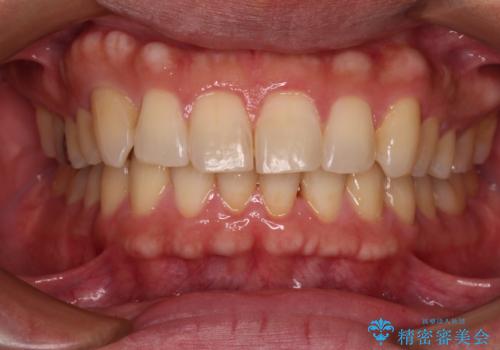

- 口元の突出感と口の閉じにくさを気にして来院された患者様です。

上下左右第一小臼歯4本を抜歯し、ワイヤー装置にて口元を引っ込めるよう矯正治療を行うこととしました。

ご友人などがびっくりするほど口元の突出感を改善することができ、患者様には大変満足していただきました。